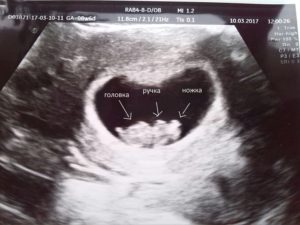

Замершая беременность на УЗИ — фото:

Прошла еще одна неделя. Перчинка стала горошинкой с «внушительными» размерами 8-12 мм. Эмбрион активно развивается: закладываются основы многих внутренних органов, формируются полушария мозга, головка визуально обретает черты лица.

Все это, с явным уже сердцебиением около 150 ударов в минуту, врач-узист зафиксирует при осмотре и покажет счастливой маме.